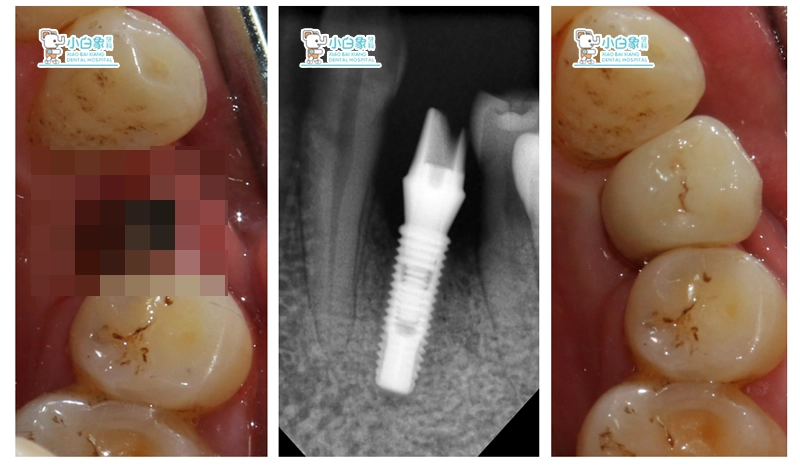

图片2

治疗过程:34必兰局麻下,切开翻瓣,在生理盐水冷却下,先锋钻,扩孔钻逐级备洞,植入美格真4.0*11.5mm种植体一枚,颊侧植骨+GBR,严密缝合。